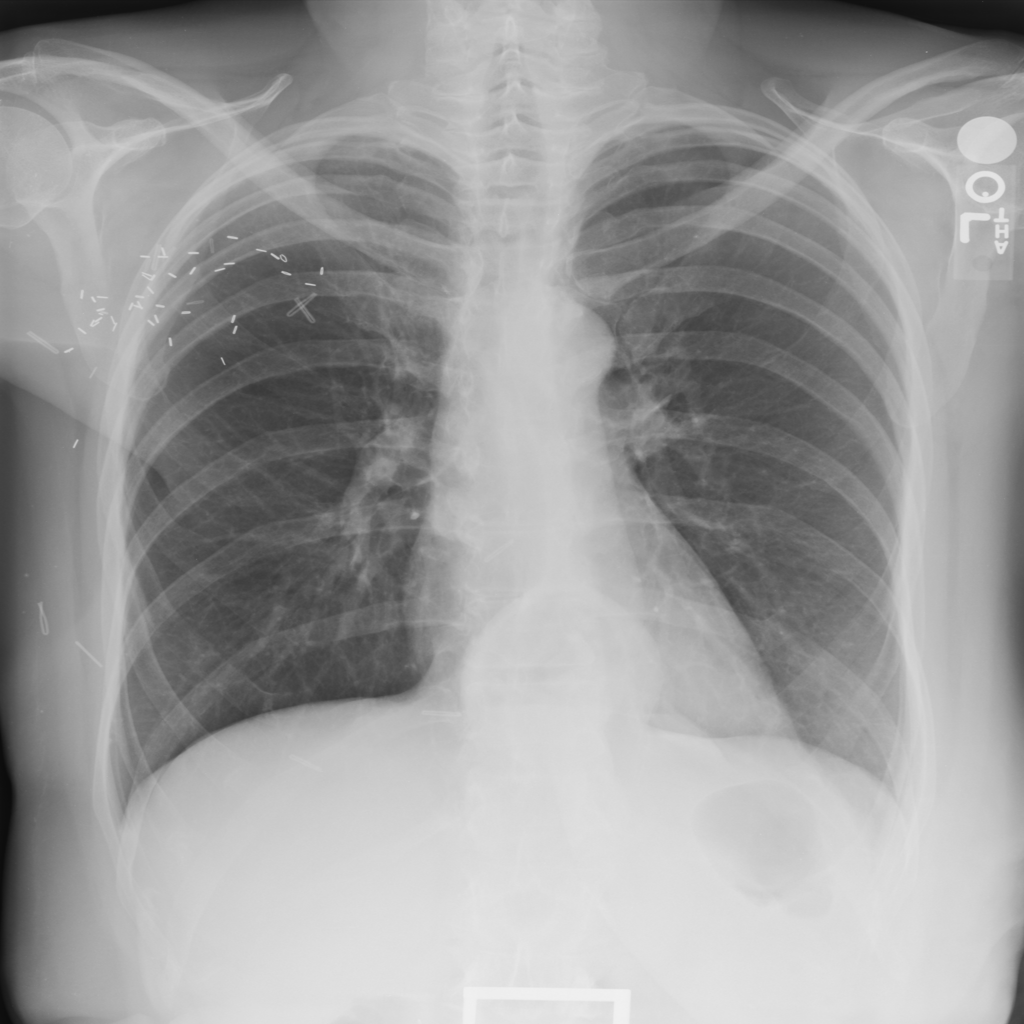

PAT-C048 · IMG-001Hernia

PAT-C048 · IMG-001

PA